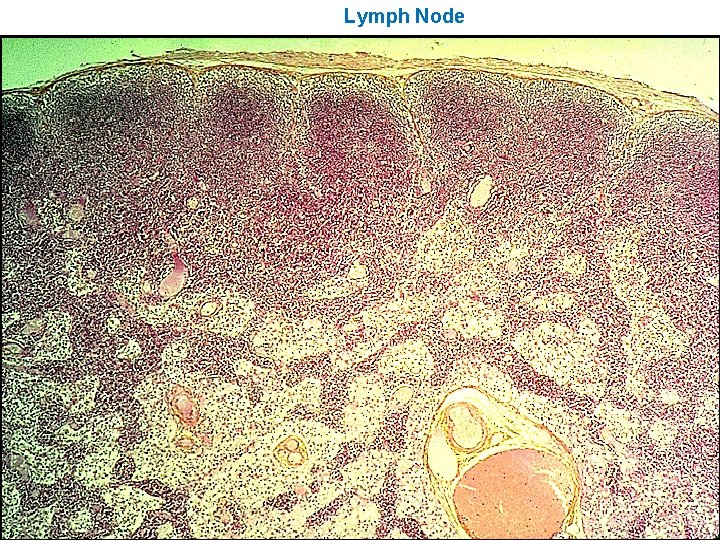

LYMPH NODES These are the smallest but most numerous encapsulated lymphoid organs. Scattered in groups along lymphatic vessels , they act as in-line filters of the lymph, removing antigens and cellular debris and adding Igs. Lymph nodes are bean-shaped structures with convex and concave surfaces. The parenchyma consists of a peripheral cortex, adjacent to the convex surface, and a central medulla lying near the depression (hilum) in the concave surface. The connective tissue capsule gives off trabeculae that penetrate between the cortical nodules and subdivide the cortex. Cortex. The cortex is dark-staining owing to the presence of tightly packed lymphocytes. These are suspended in a reticular connective tissue network and arranged as a layer of typical secondary lymphoid nodules (containing primarily B lymphocytes) with germinal centers. The cortex also contains reticular cells, antigen-presenting follicular dendritic cells, macrophages, a few plasma cells, and some helper T cells.

Medulla. Lighter staining than the cortex, the medulla is composed of cords of lymphoid tissue (medullary cords) separated by medullary sinuses. The lymphocytes are mainly small, less numerous than in the cortex. The cords are also rich in reticular cells and fibers and contain many plasma cells that have migrated from the cortex. Paracortical zone. This is the T-dependent region, lying between the cortical lymphoid nodules and the medulla. It contains mainly T lymphocytes suspended in a reticular connective tissue. B lymphocytes, plasma cells, macrophages, and antigen-presenting interdigitating dendritic cells may also be present. Lymphatic vessels. Sinuses (subcapsular, peritrabecular, medullary). Functions: 1. Filtration of lymph 2. Lymphocyte production (lymphopoiesis). 3. Immunoglobulin production.